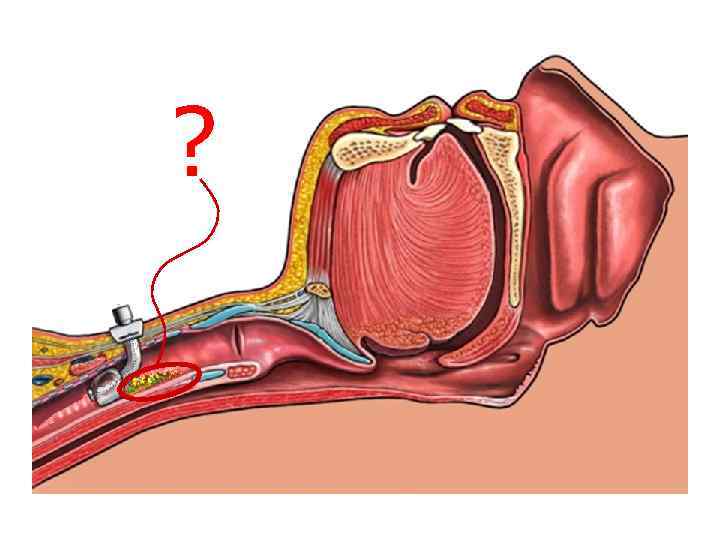

Интубированный больной надгортанник Интубационная трубка как распорка, позволяет стекать содержимому ротоглотки в трахею

Интубированный больной надгортанник Интубационная трубка как распорка, позволяет стекать содержимому ротоглотки в трахею

секрет

секрет

Санация надманжеточного пространства Muscedere J, et al. Crit Care Med 2011

Санация надманжеточного пространства Muscedere J, et al. Crit Care Med 2011

Профилактика и лечение инфекционновоспалительных изменений гортани и верхних отделов трахеи Дренаж надманжеточного пространства Portex

Профилактика и лечение инфекционновоспалительных изменений гортани и верхних отделов трахеи Дренаж надманжеточного пространства Portex

Канал для санации надманжеточного пространства

Канал для санации надманжеточного пространства